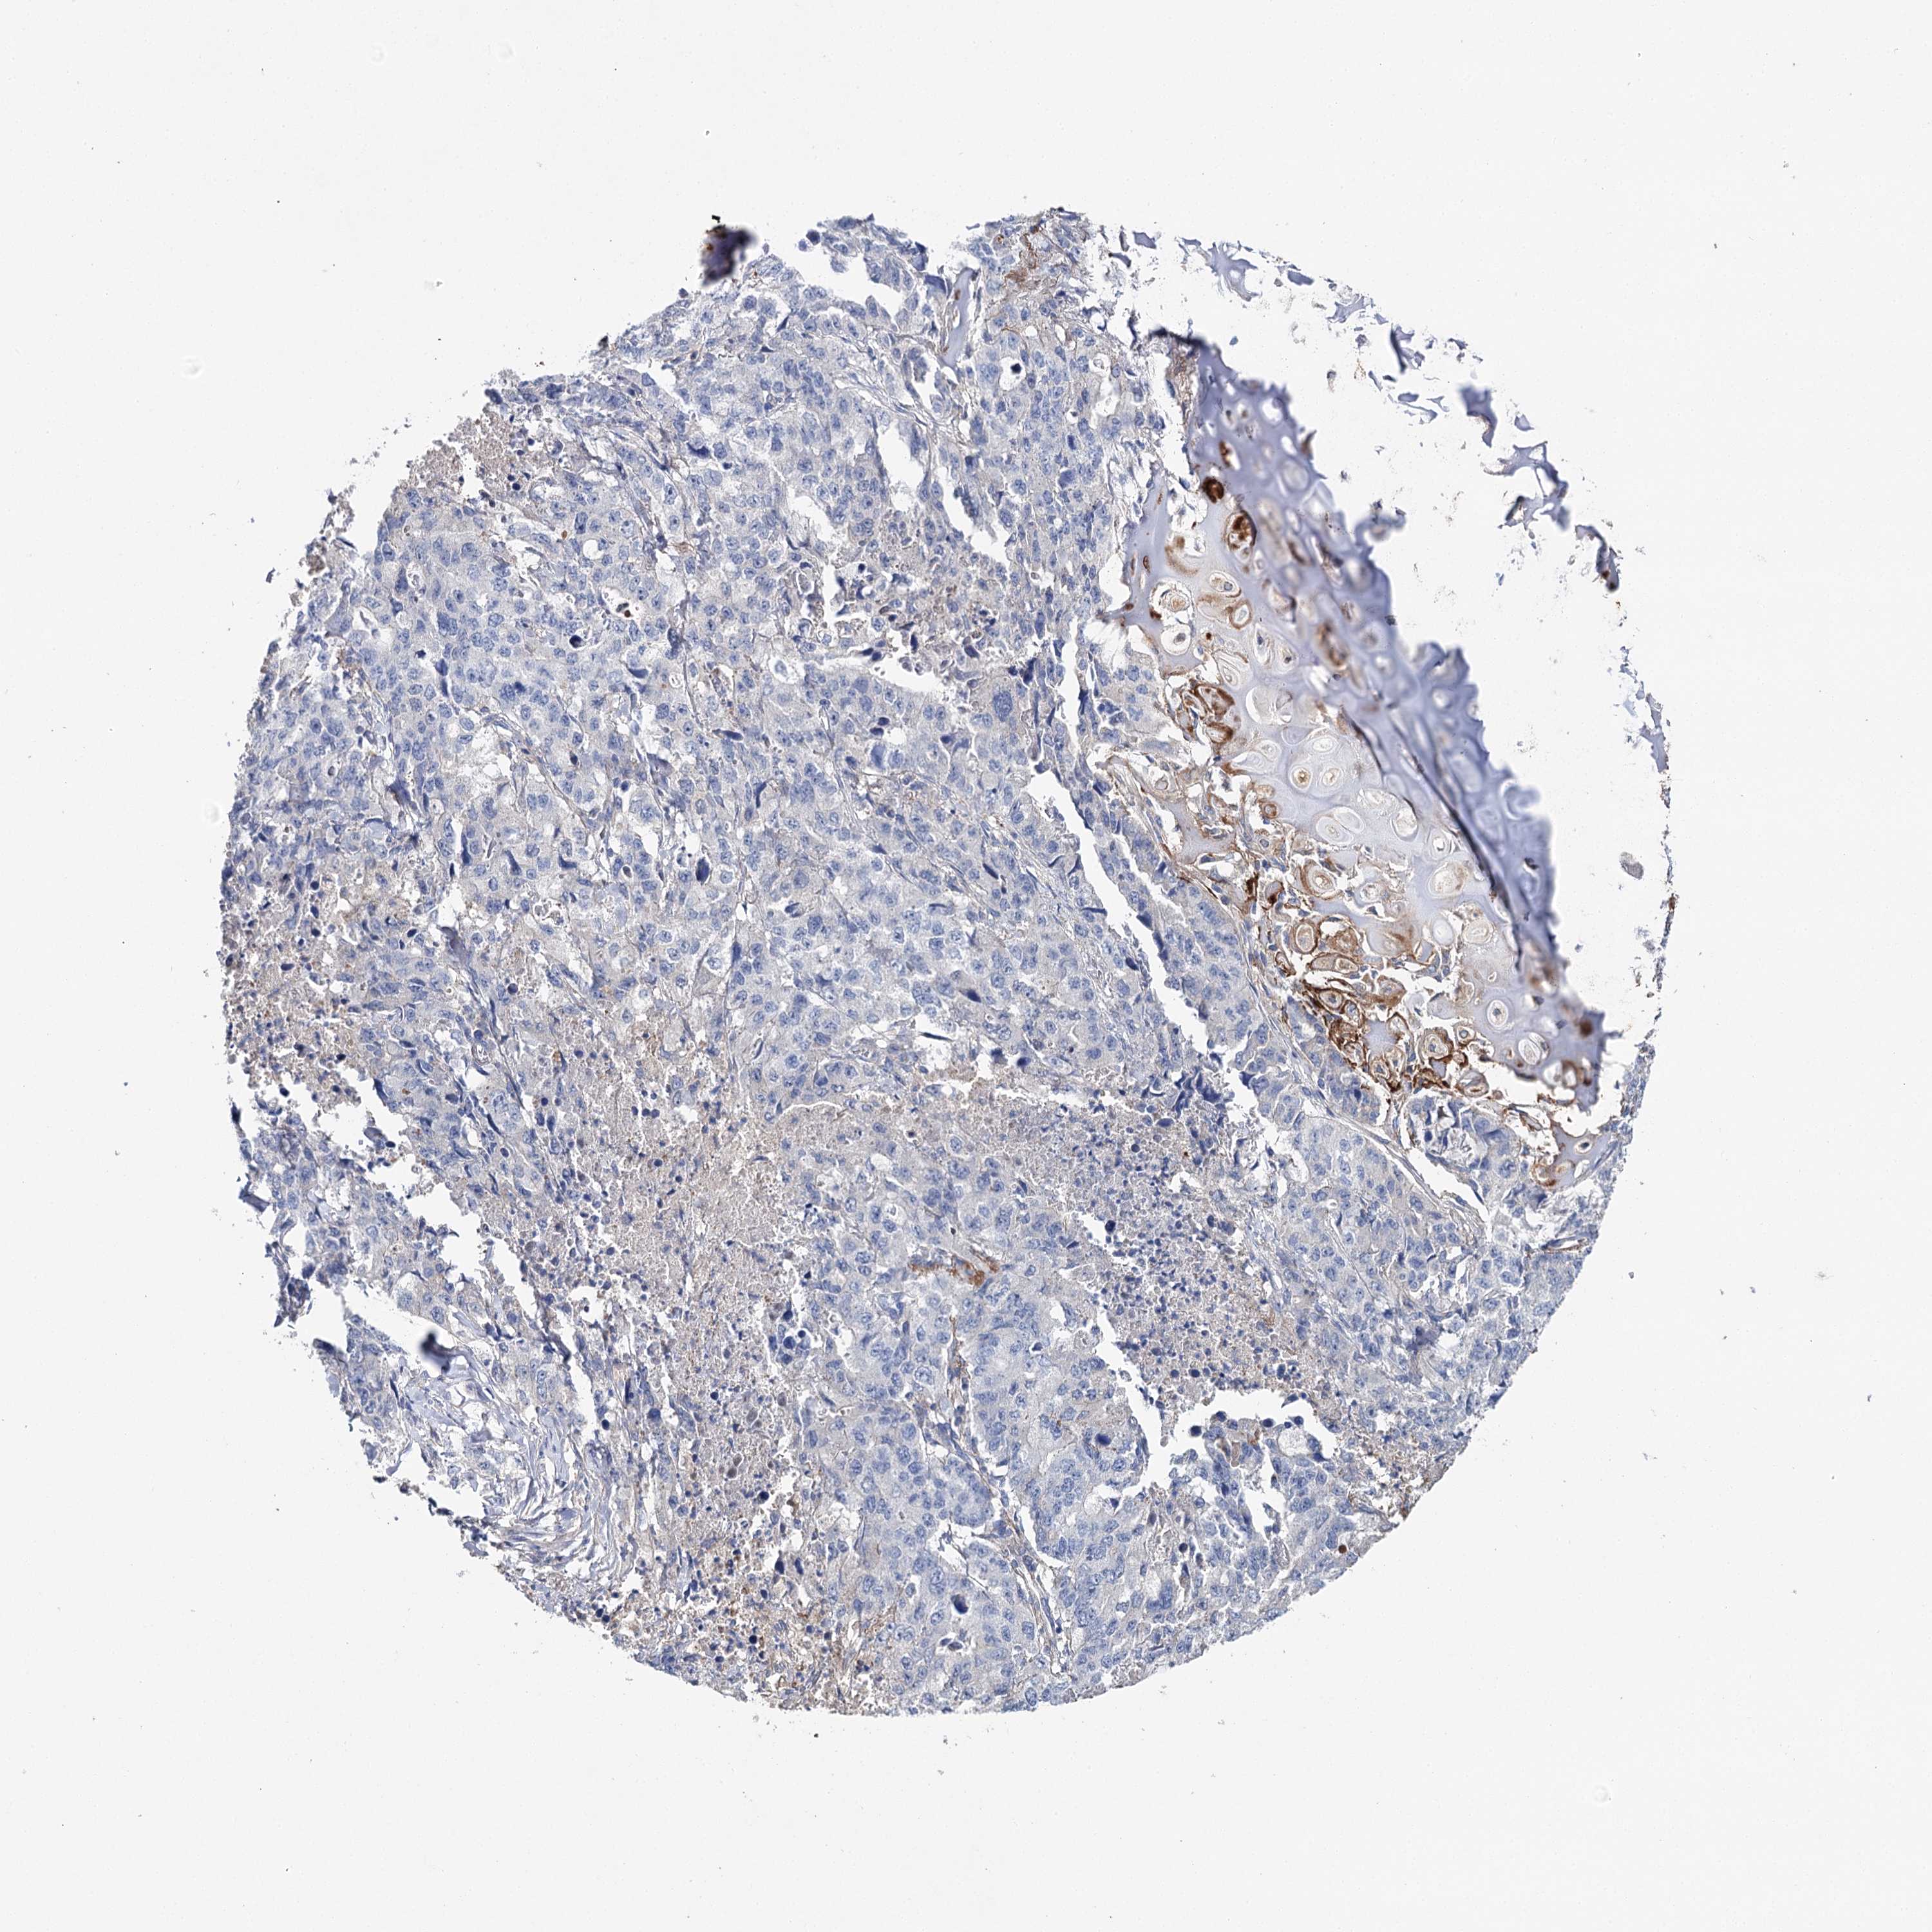

CANCER LUNG CANCER Show tissue menu

LUAD TCGA LUAD VALIDATION LUSC TCGA LUSC VALIDATION PROTEIN LUAD CPTAC PROTEIN LUSC CPTAC PROTEIN EXPRESSION

ANTIBODIES

AND

VALIDATION